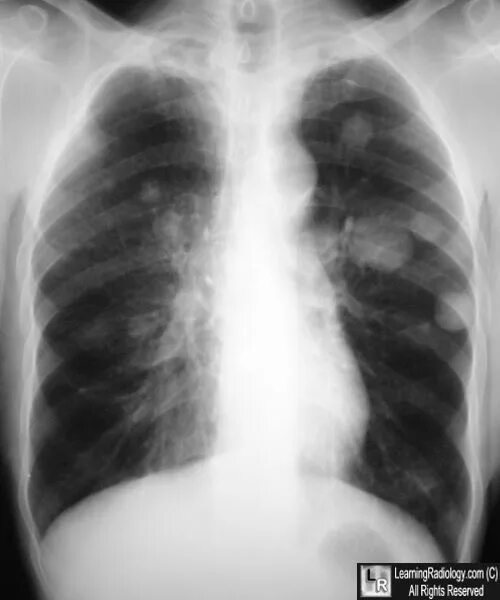

Метастазы 3 стадии